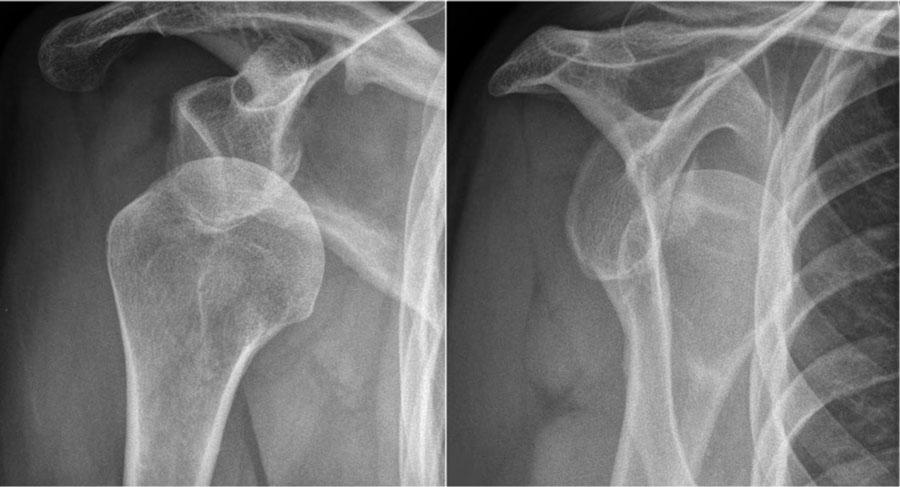

Hình ảnh của một bệnh nhân khác bị trật khớp ra sau.

Trên phim chếch qua xương bả vai (transscapular-Y), chỏm xương cánh tay bị di lệch ra sau.

Lưu ý khoảng cách giữa chỏm xương cánh tay và ổ chảo trên phim thẳng (AP) rộng bất thường.

Trên các hình ảnh, quan sát thấy trật khớp ra sau kèm gãy xương.